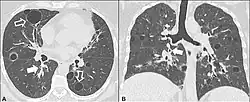

| CT scan of the lung showing bullae in the lower lung lobes of a subject with type alpha-1-antitrypsin deficiency. There is also increased lung density in areas with compression of lung tissue by the bullae. | |

A focal lung pneumatosis is an enclosed pocket of air or gas in the lung and includes blebs, bullae, pulmonary cysts, and lung cavities. Blebs and bullae can be classified by their wall thickness.[1]

- A bleb has a wall thickness of less than 1 mm.[2] By radiology definition, it is up to 1 cm in total size.[3] By pathology definition, it originates in the pleurae (rather than in the lung parenchyma).[4]

- A bulla has a wall thickness of less than 1 mm.[2] By radiology definition, it has a total size of greater than 1 cm.[3] By pathology definition, it originates in the lung parenchyma (rather than in the pleurae).[4]

The most common disease causing blebs or bullae is paraseptal emphysema though centrilobular emphysema may sometimes be involved.[1]

- Alpha 1-antitrypsin deficiency[6]